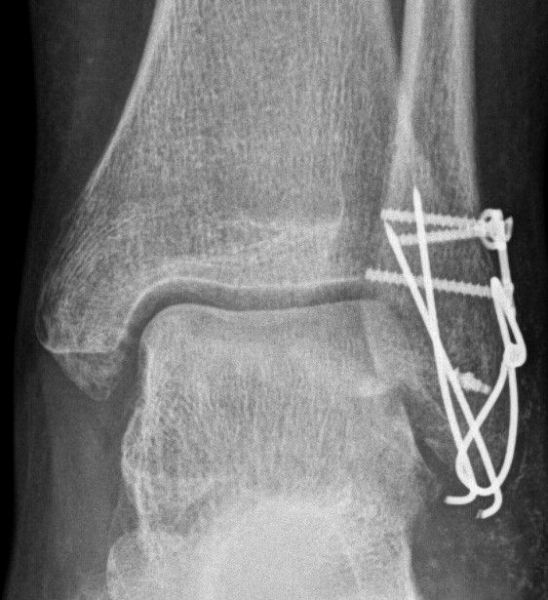

3. Nonunion distal tip of the left lateral malleolus in a 47-year-old female.

Treatment: Open reduction internal fixation with the use of specific grafts

I. Before surgery, anteroposterior view of the ankle II. Four months post-surgery, anteroposterior view of the ankle shows the metal work and the union of fracture